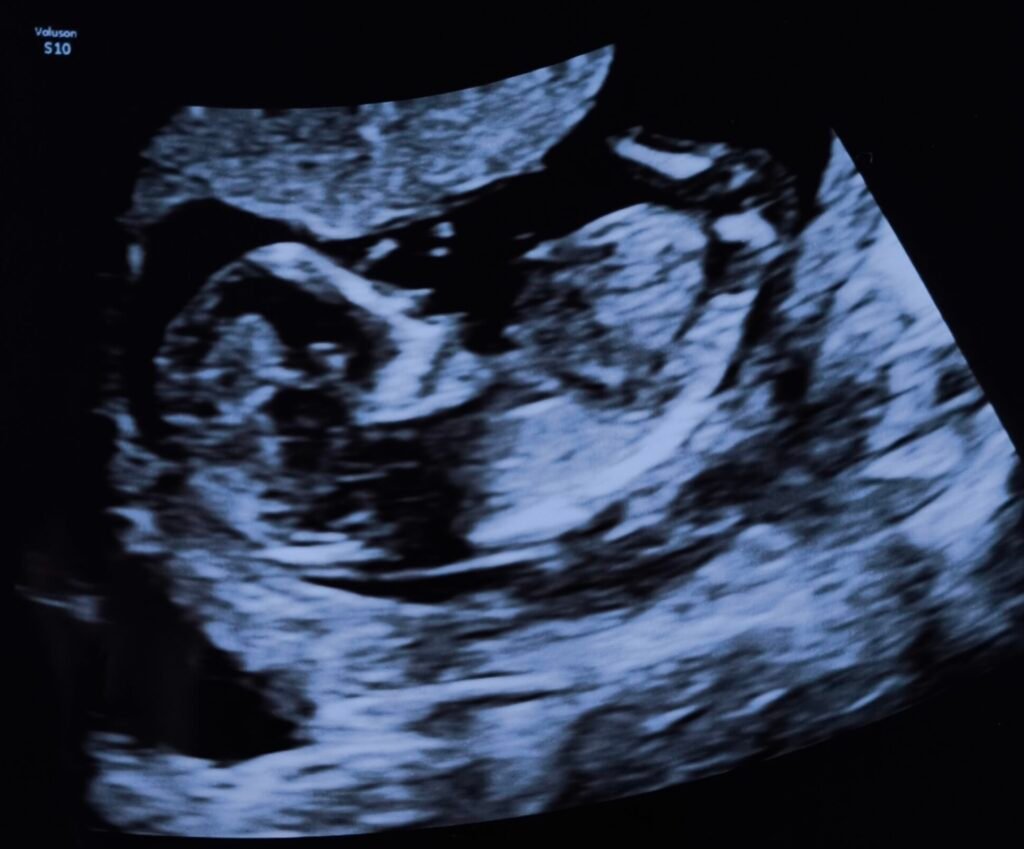

Third Echo – Week 13

23/09/2025

During the sonogram, for the first time, without introduction, the heartbeat!

Admittingly, a little confronting to realize that this moving picture is actually alive and kicking by hearing the heartbeat thumping at 180 bpm like ‘Living la vida loca’ inside you.

Baby is baking at 74mm, 80gr for 13 weeks and 5 days. The back is closed, the heart is pumping around blood in 4 chambers and the brain has 2 hemispheres. Keep it up little munchkin!